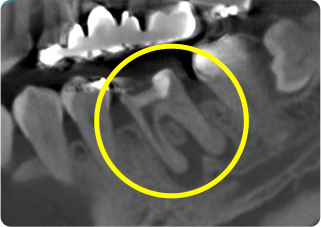

症例

術後

主訴 奥歯で噛むと痛い

治療期間/回数 1ヵ月、3回

価格(税込) 88,000円

リスク・副作用 病変再発、歯根破折の可能性

ポイント う蝕検知液を用い、むし歯の取り残しが無いようにし、ラバーダム防湿を行い、無菌的に根管治療を行った。根管充填材は、殺菌作用の強い保険適応外のMTAセメントを使用した。